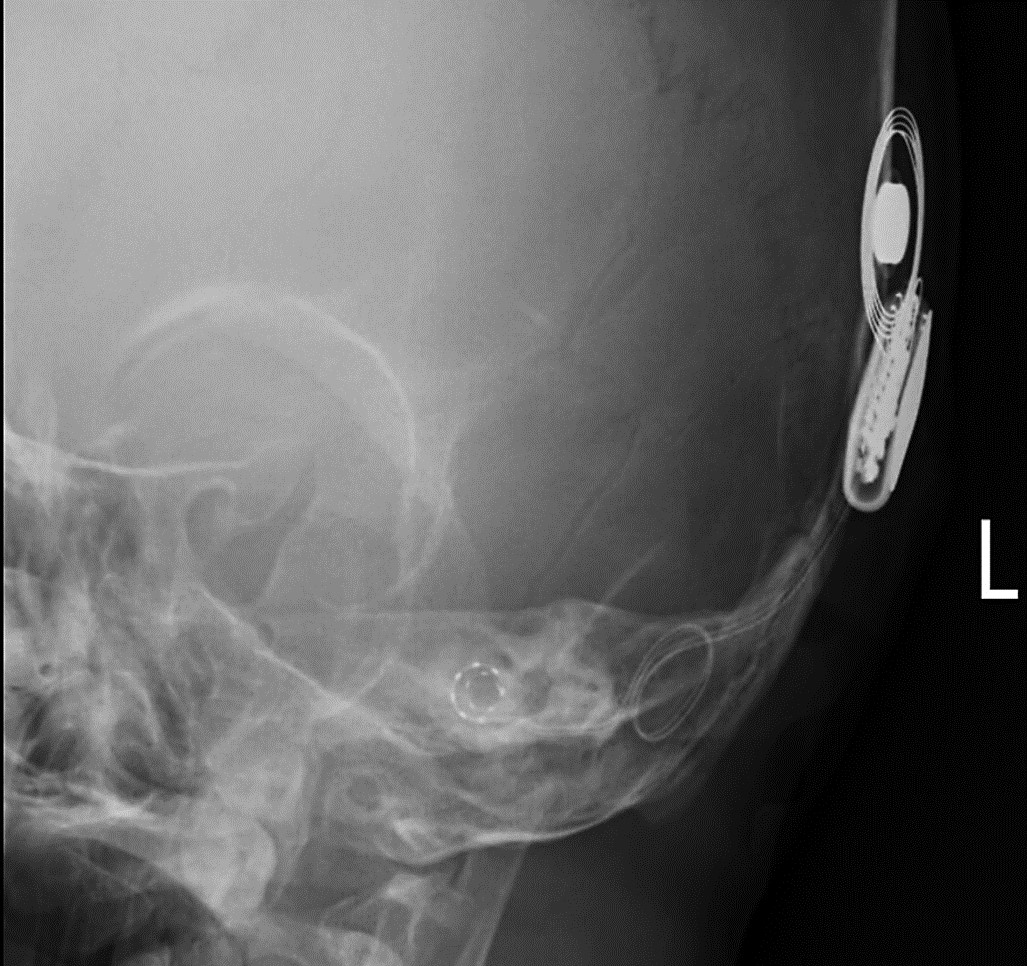

除了微小切口,微创手术更要重的就是手术路径的微创,在植入人工耳蜗电极时,有两种手术植入方式,一种是开窗植入,需要在传统的耳蜗开一个小孔,额外使用钻头进行鼓岬开窗,这种开窗植入对耳蜗完整性的破坏是肯定的,也会对残余听力造成更大的损伤。而另一种手术方式就是软电极圆窗植入,通过耳蜗自身存在的圆窗,将电极近乎无创、十分顺滑的植入耳蜗。既不会破坏耳蜗内的复杂的神经组织,同时也很好的将电极植入到了耳蜗精准的位置,实现电极全覆盖植入,保留患者的残余听力的同时获得更佳的聆听效果。在手术过程中,通常都会开启术中监测,以确保手术的精准性和安全性。

耳蜗电极完全覆盖(2圈以上)

术中监测良好